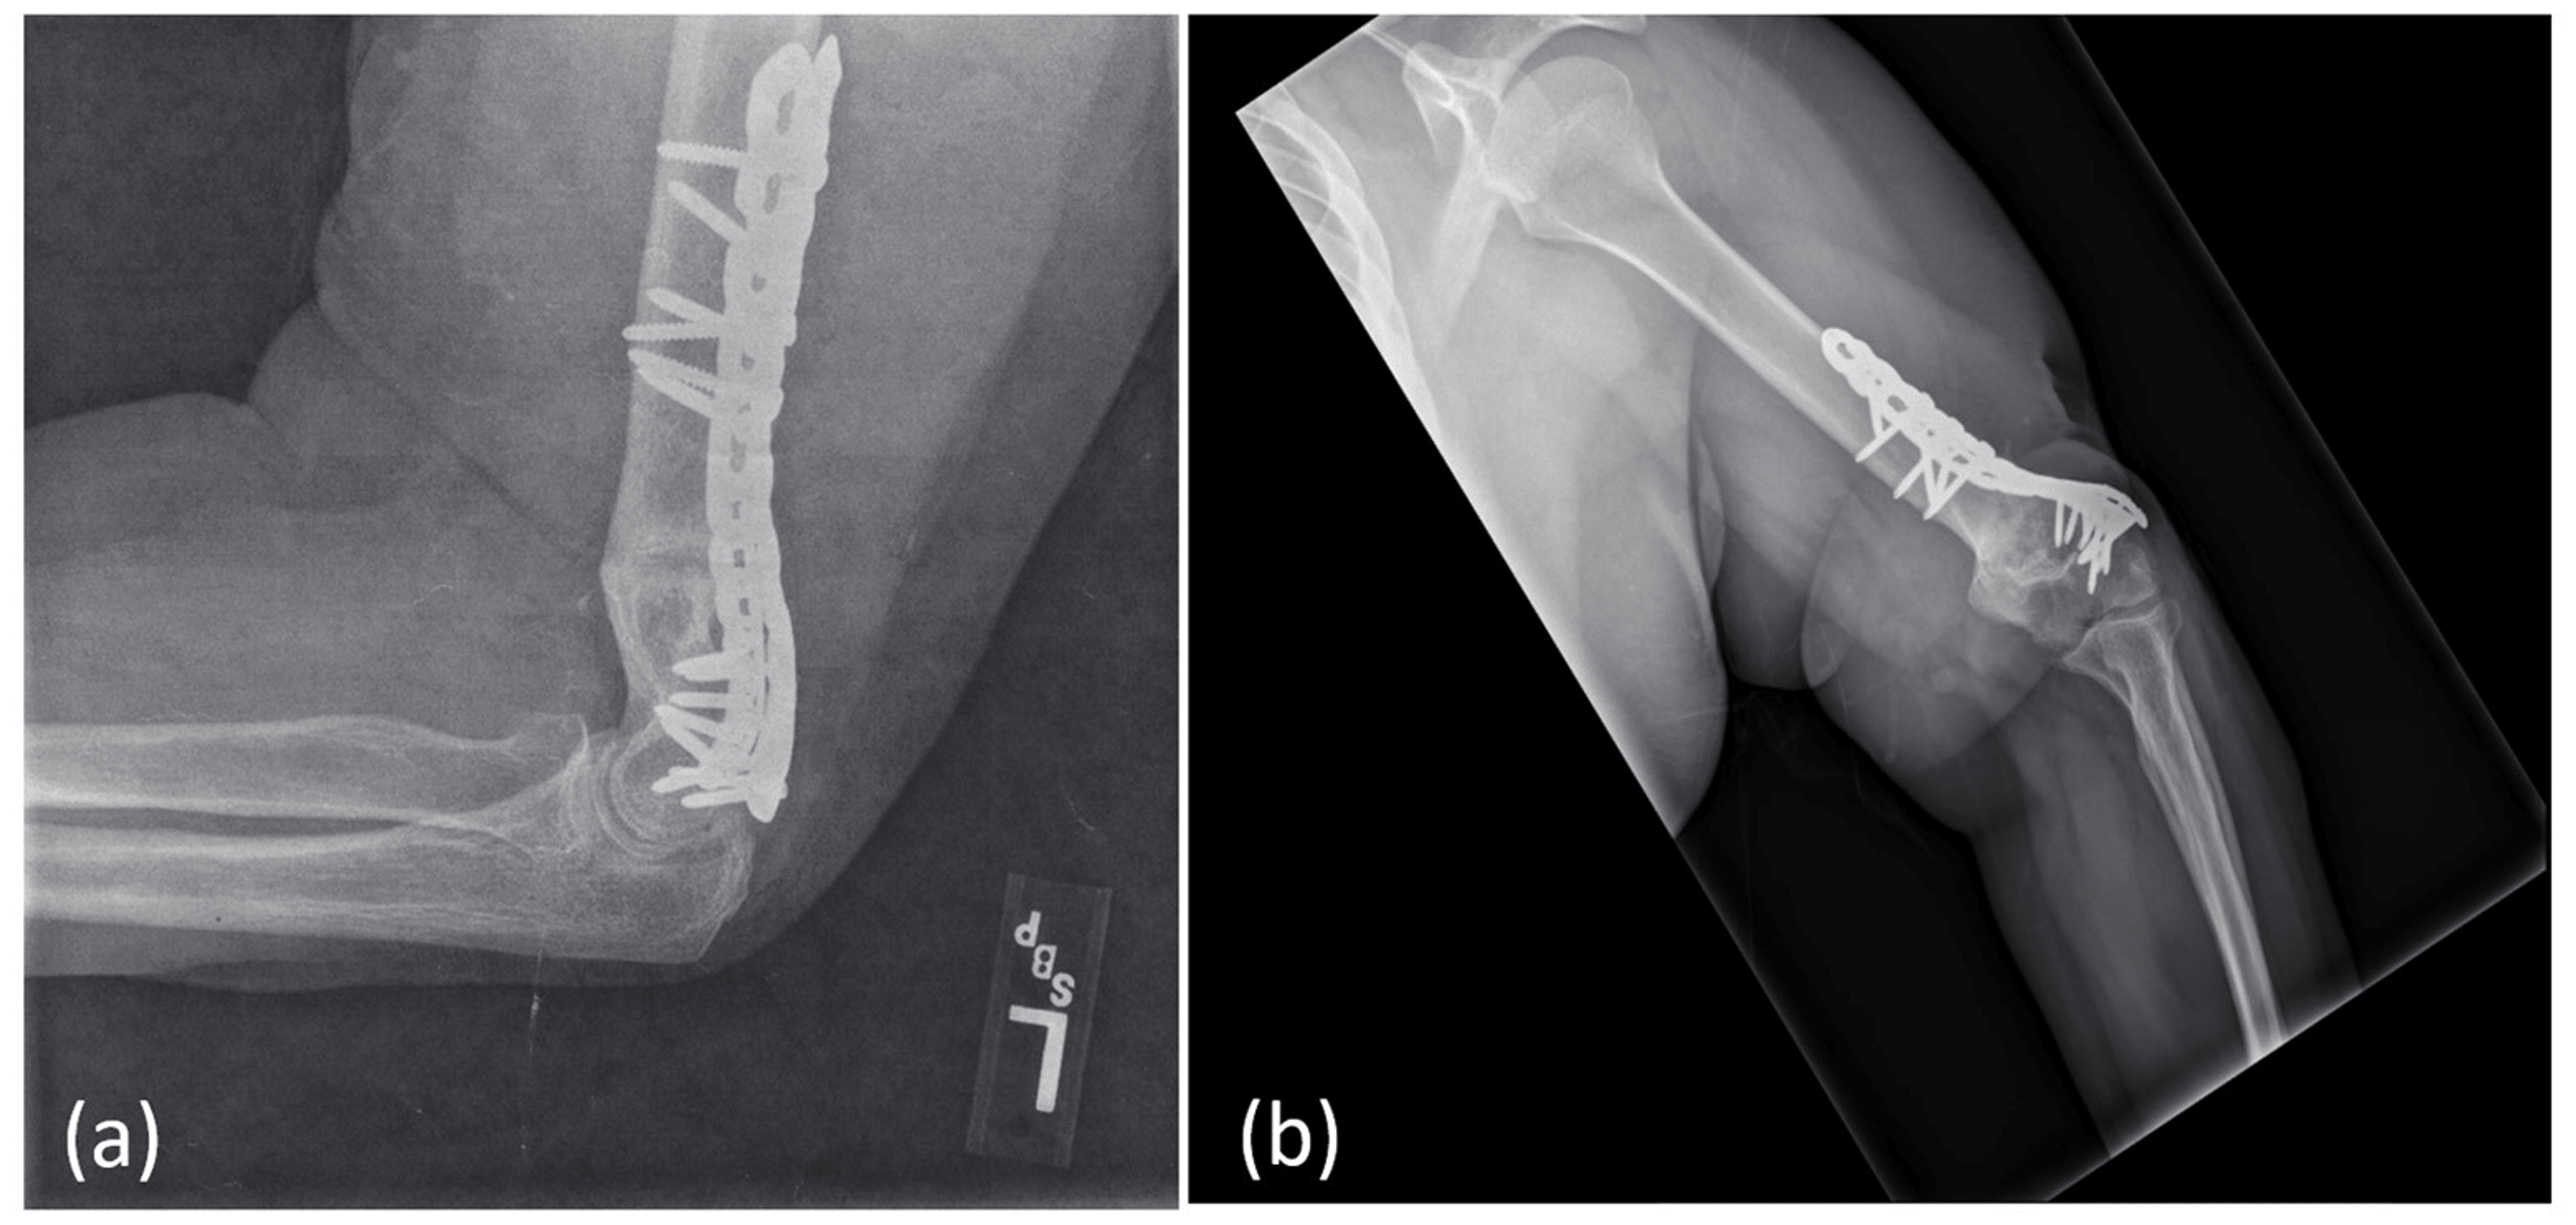

Traumatic Humeral Shaft Nonunion With Ulnar Nerve Transection An Non-Union Radiological Features Solid bone healing will not occur without further treatment or. Although edema is evident in the adjacent marrow, there is no abnormal enhancement postgadolinium to suggest infection. Emerging evidence from the literature is discussed in this review with a focus on ct and ultrasound as useful imaging. Important to discern injury mechanisms, non operative interventions, baseline metabolic, nutritional or immunologic. Non-Union Radiological Features.